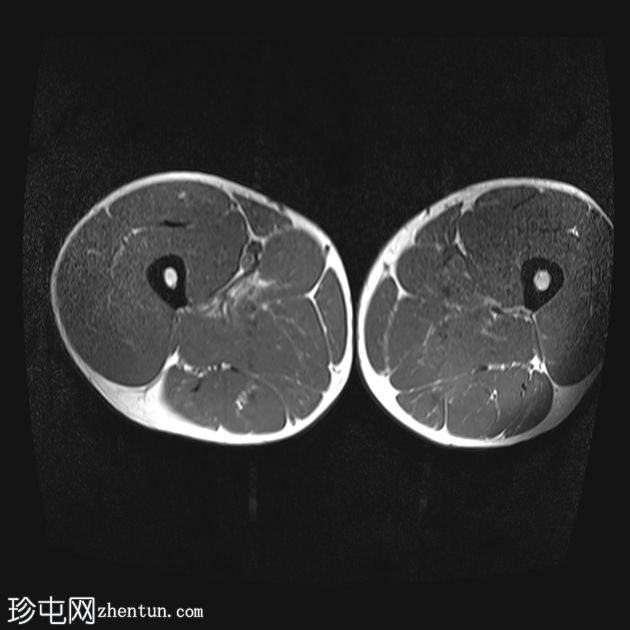

轴位

T2加权像

内收长肌和内收短肌中远侧外侧可见羽状改变和肌内水肿,主要累及内收大肌,长15厘米,宽4厘米。未见明显血肿或完全性肌纤维撕裂。

后腱膜、邻近神经血管交界处及邻近肌间隙可见积液,少量积液向外侧扩散,沿肌间隙到达大腿中远侧。

内收肌腱完整,骨性附着点清晰可见,肌腱轻度增厚,中部可见腱周水肿;未见撕裂。